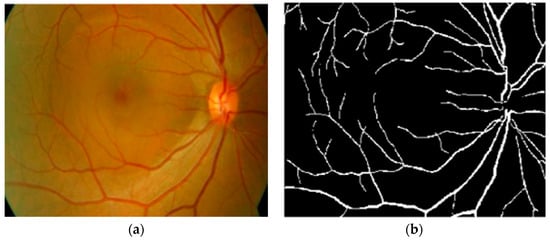

2.2. Blood Vessel Extraction

The detection of structural changes of the retinal vascularization system in color fundus angiography is a critical and repetitive task for clinical personnel. Accurate vessel segmentation leads to fast and reliable assessment by the DR-CAD system. Additionally, the detection of geometrical-based vessel features and secular changes of vessels, as shown in Figure 4, assists less experienced doctors in the accurate diagnosis of DR. Retinal vessel segmentation methods in the literature can be divided into three groups: Supervised-based, unsupervised-based, and mathematical morphology-based methods.

Figure 4.

A sample of a fundus image showing secular changes of vessels.

Kaur and Mittal in [42] developed a vascular detection system using fundus images. Preprocessing was initially done to normalize the images from low contrast and non-uniform illumination. They extracted the pixel intensity and geometric features using a matched filter and then fed these to a neural network classifier to classify vessels from a non-vascular region. The authors obtained an accuracy of 95.45%. Their intermediate results are shown in Figure 5. However, the approach had less significance in the detection of lesions that contribute to an incorrect vascular structure. Neto et al. in [43] presented an unsupervised coarse segmentation approach for vessel detection with an average accuracy of 87%. They incorporated multiple concepts, i.e., mathematical morphology, curvature, and spatial dependency, with the coarse-to-fine method to accurately define thin and elongated vessels from vessel pixels. However, the algorithm was unsuccessful in the determination of the vessel diameter and was also found to be less satisfactory at segmenting vessel structures on low contrast images. To detect changes in the structural and micro-pattern of vessels, several textural descriptors were applied to extract vascular features. These features were fed into a forest classifier to classify true vessel points from non-vessel patterns [44]. A sensitivity (SE) of 96.1% and specificity (SP) of 92.2% in the classification of true vessel points was reported. A comprehensive review of supervised-related, unsupervised-related, image processing-related, and data mining-related algorithms is presented in [45,46,47] with high vessel segmentation results.

Figure 5.

(a) Original image; (b) ground truth; (c) proposed vasculature extraction [42].